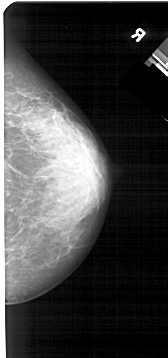

A_1280_1.LEFT_MLO

LEFT_MLO LINES 5491 PIXELS_PER_LINE 2446 BITS_PER_PIXEL 12 RESOLUTION 43.5 OVERLAY